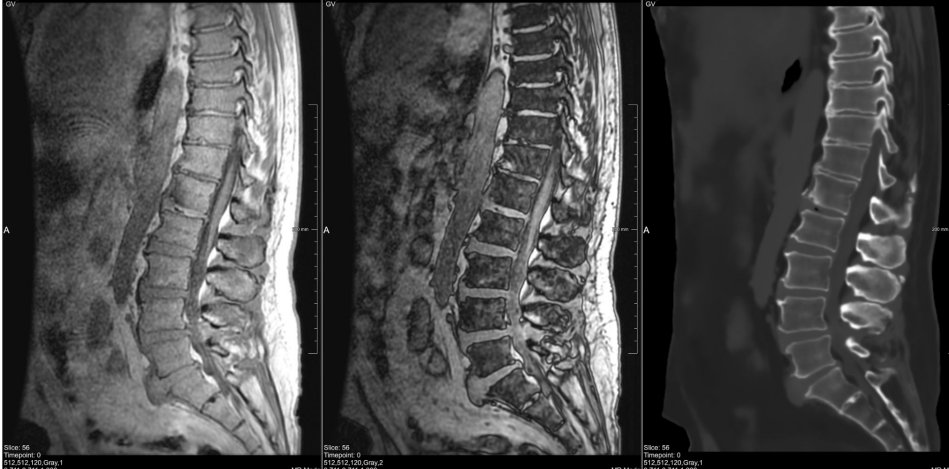

7D MRVision

7D MRVision™ utilizes MRIguidance’s BoneMRI™ software to generate a synthetic CT from an MRI scan that can be used for surgical planning and spinal navigation with the 7D FLASH™ Navigation System Spine Module. Traditional spine navigation requires a preoperative CT or intraoperative radiation for image acquisition and registration. 7D MRVision is the first and only solution that eliminates radiation from the entire navigation workflow.